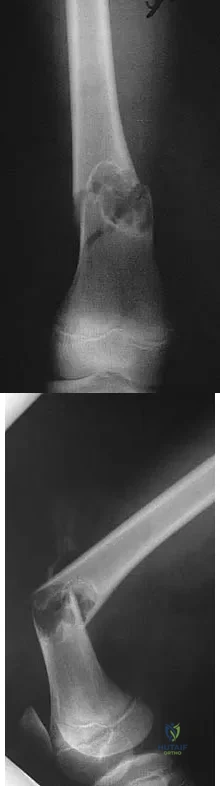

Figure 2 shows the lateral radiograph of an 8-year-old boy who sustained an acute injury to the elbow after falling down the stairs. Management should consist of

Explanation